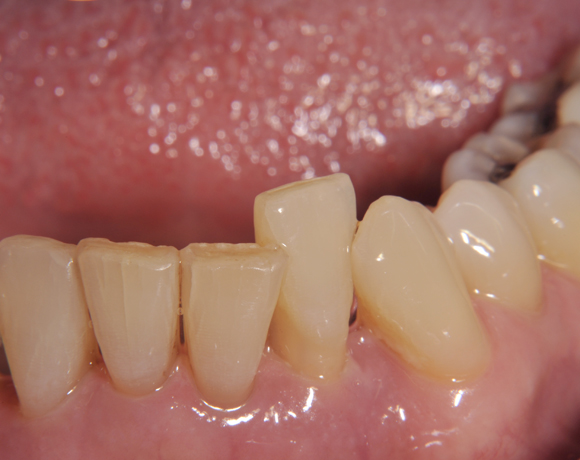

Am Beispiel dieses Patientenfalls wird gezeigt wie ein Einzelimplantat für den Unterkieferfrontzahn 33 eingesetzt wird.